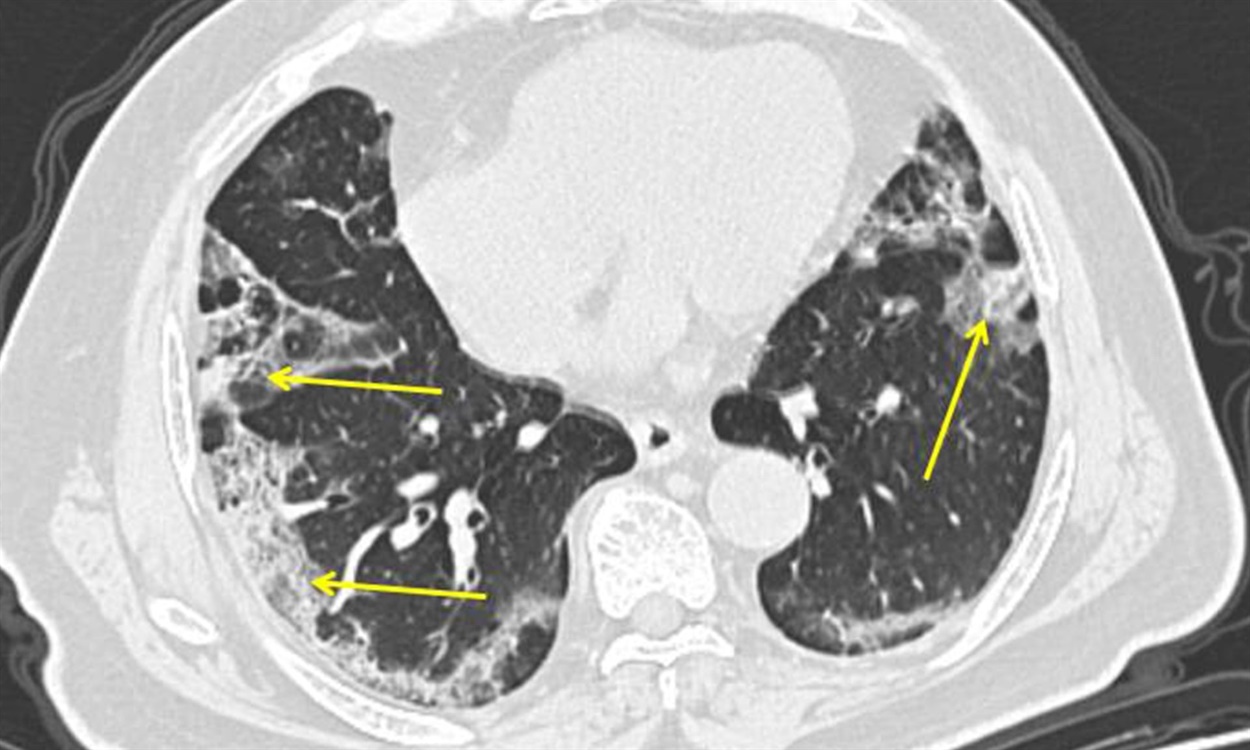

КТ-знімок людини, хворої на коронавірус. Пневмонія, спричинена новим важким гострим респіраторним коронавірусом, може проявлятись як характерні мутні плями на зовнішніх краях легень, позначені стрілками

Якщо ситуація погіршиться, інфекція потрапляє до всіх структур, які беруть участь в газообміні. Таким чином збудник інфекції опиняється у повітряних мішечках (альвеолах) на дні легенів. Якщо вони потім запалюються, це викликає потрапляння рідини та клітин в легені — і все закінчується пневмонією.

Як зазначає Джон Вілсон, є докази того, що пневмонія, викликана Covid-19, може бути особливо важкою. У випадку коронавірусної пневмонії, як правило, вражені усі легені, а не лише невеликі частини.